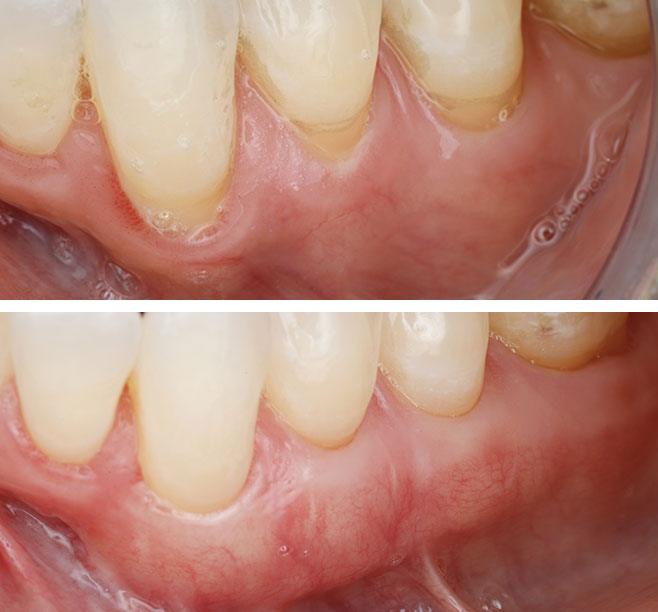

Gum Recession Treatment

in Manhattan Beach CA

Gum recession exposes tooth roots, causing sensitivity, cosmetic concerns, and increased risk of decay or tooth loss. At Precision Periodontal and Implant Center, we provide targeted treatments designed to halt progression and rebuild lost gum tissue for improved health and aesthetics.

- Gum Grafting: Dr. Ivanov expertly transplants healthy tissue to cover exposed roots, reinforce gum structure, and restore a natural gum line.

- Pinhole Surgical Technique: A minimally invasive procedure that adjusts existing gum tissue without incisions or sutures for faster recovery.